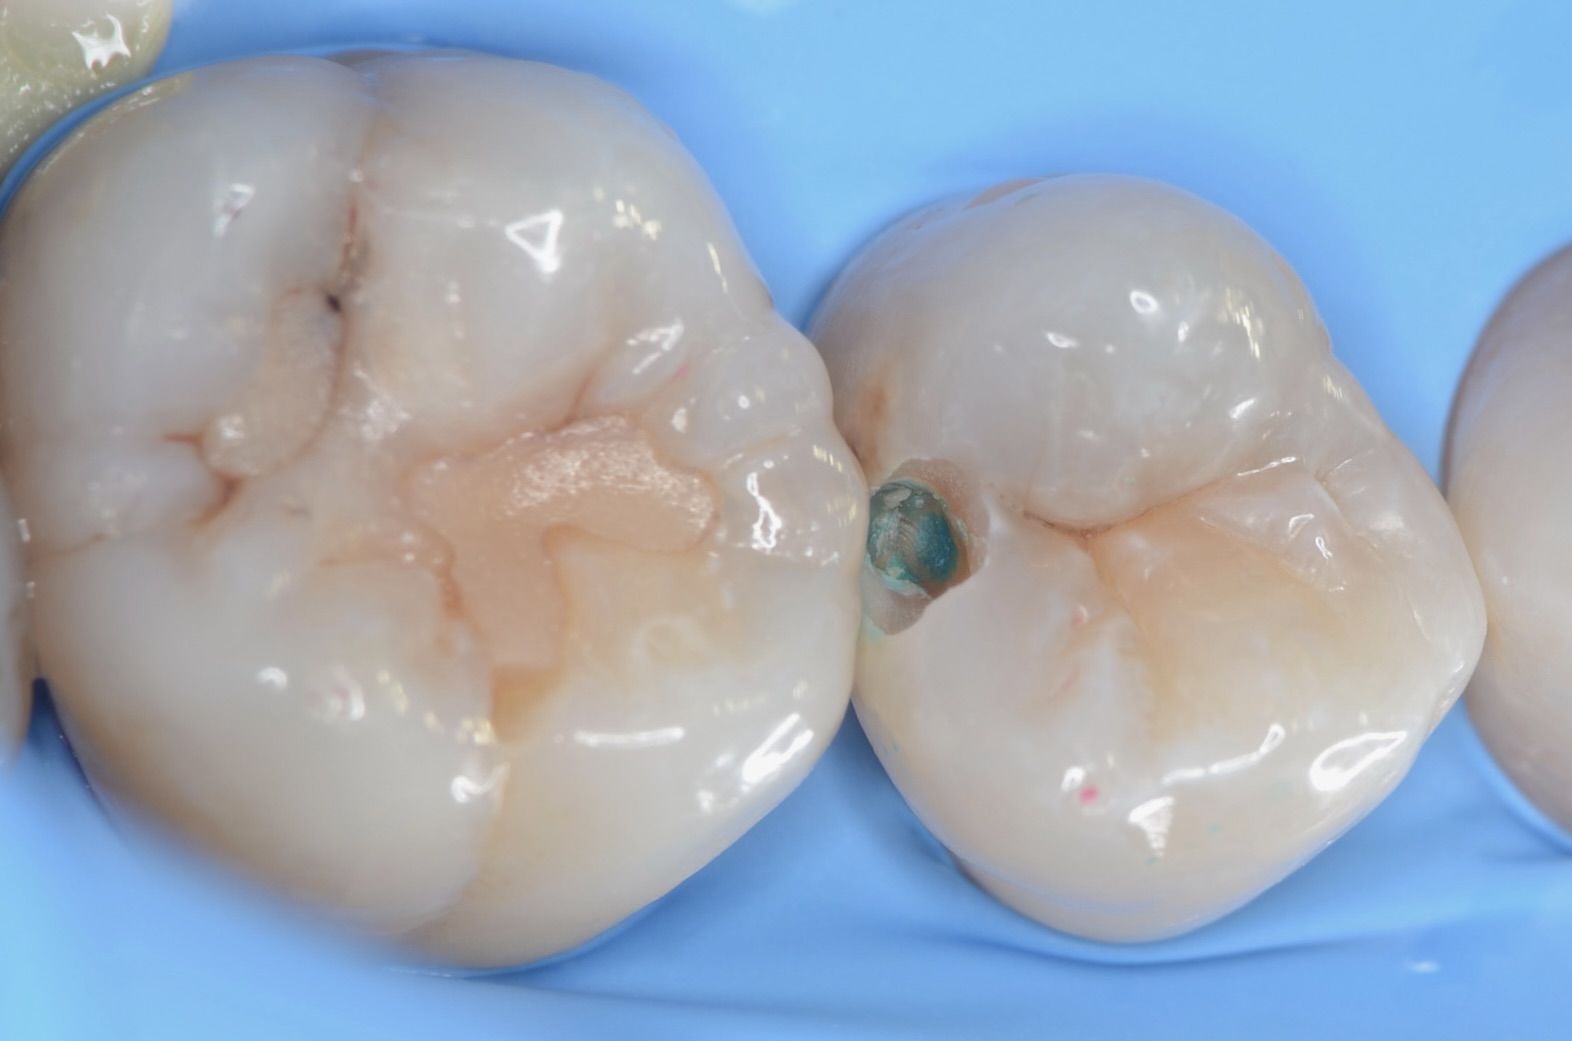

少し歯を削る

虫歯のある部分を上記のチェックで確認した後、少しだけエナメル質を削ったところ、内部に虫歯が広がっているのを確認できました。 -

6番近心

5番の削った部分から覗くと隣の歯にも虫歯を認めます。初期虫歯と思われる所見でも、実際に歯を削ってみると結構虫歯は広がっているものです。これをフッ素塗布や家庭でのブラッシングやフロスで進行を止めることはできません。 -

5番虫歯除去終了

青い齲蝕検知液で虫歯を染めて染まった部分を削ります。この工程を青く染まらなくなるまで歯にできるだけダメージがないように優しい力で丁寧に行います。この作業は時間がかかります。保険診療の短い時間で行うことは無理があります。 -